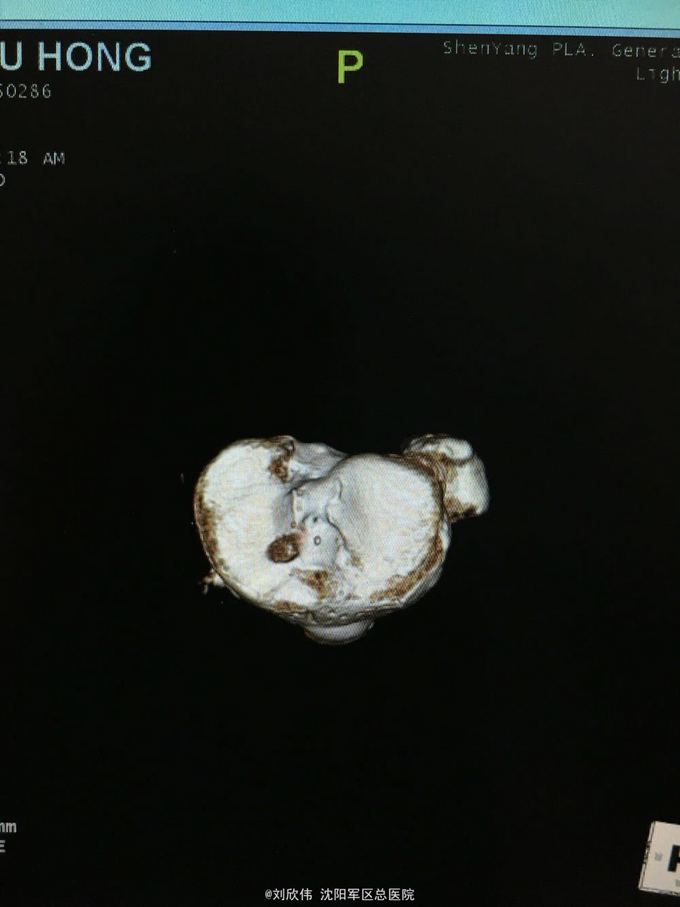

男性,44岁,摔伤所致,左膝。诊断如题

前抽屉,lachman,轴移阳性,外侧应力试验因疼痛无法进行

诊断如题,关节镜解决acl,mcl给予支具保守治疗